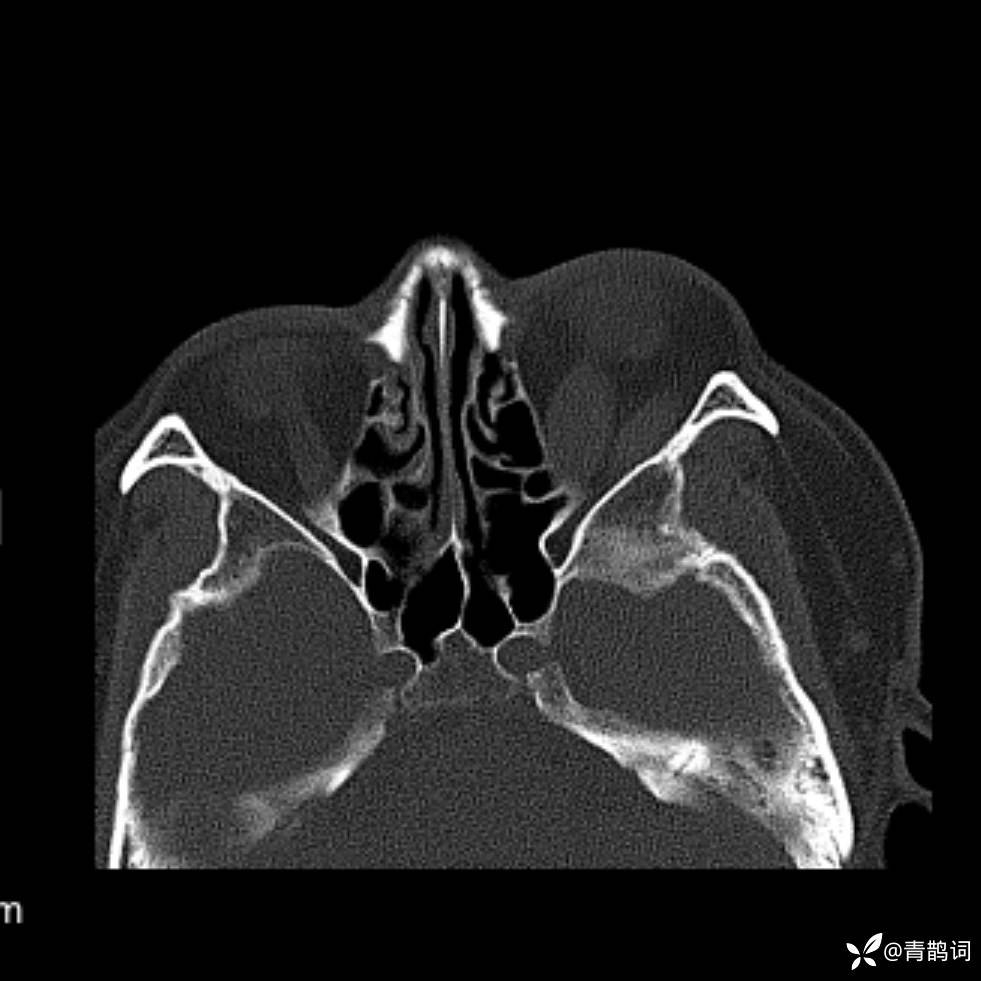

患者年龄:30岁。

患者性别:男。

简要病史:左颜面部肿胀2年,反复咳嗽咳痰,逐渐加重。

辅助检查